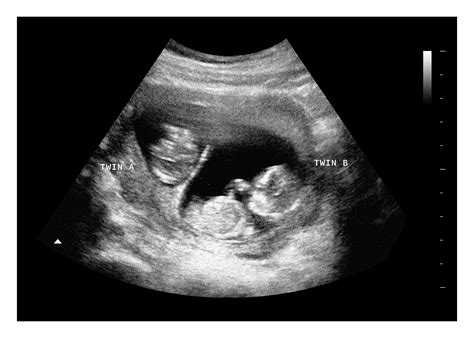

• Checking for multiple pregnancies.

• Multiple Pregnancies: The scan can confirm the presence of twins, triplets, or more, and determine if they are identical or fraternal.